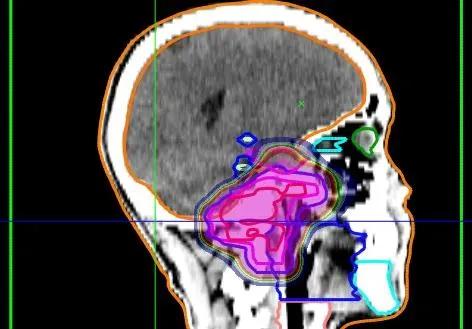

靶区勾画是精准放疗的关键步骤。医生需要通过高精度影像技术,如MRI和CT扫描,精确勾画出肿瘤的范围和位置。这不仅包括可见的肿瘤组织,还要考虑到可能的微小扩散区域。精确的靶区勾画可以确保放射线只作用于肿瘤,最大限度地保护周围正常组织。

在靶区勾画的基础上,新型照射技术的应用大大提高了治疗效果。其中,质子治疗被认为是最有前景的方法之一。与传统X射线相比,质子束具有独特的物理特性。它可以将大部分能量集中在特定深度,形成所谓的布拉格峰。这意味着医生可以将高剂量的放射线精准地投射到肿瘤区域,而对周围组织的影响最小。

另一种先进的照射技术是立体定向放射治疗(SRT)。这种技术使用多束低强度射线从不同角度照射肿瘤,使得肿瘤区域接受高剂量照射,而周围组织受到的辐射剂量较低。SRT可以作为手术前后的辅助治疗,也可以单独用于不适合手术的患者。